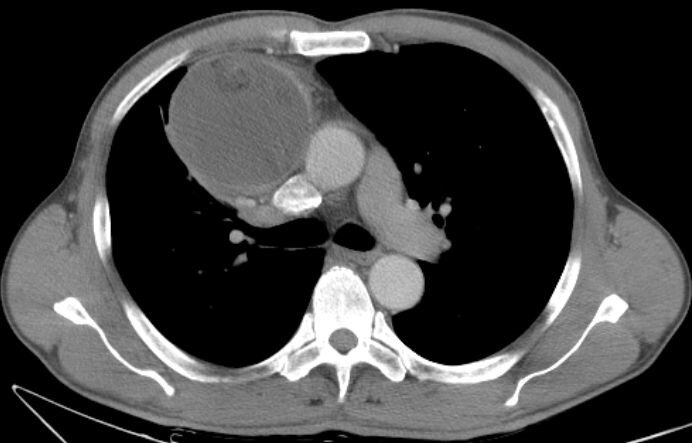

【病例】纵隔巨大支气管源性囊肿1例ct影像表现

纵隔囊肿